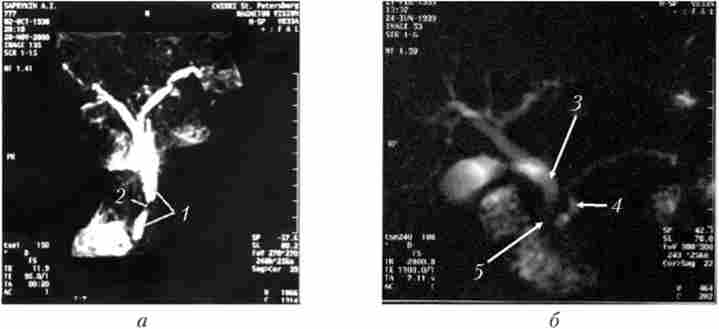

В останні роки з'явився новий неінвазивний метод - магнітно резонансна холангіопанкреатографія (Рис. 21.5), який дозволяє візуалізувати жовчні і панкреатичні протоки без інвазивних втручань і введення контрастних речовин. Це дослідження можна здійснити майже у всіх хворих, не дає ускладнень і дозволяє отримати таку ж інформацію, як і при одночасному застосуванні КТ, ангіографії та ретроградної холангіопанкреатографія (РХПГ).

Магнітно-резонансна холангіопанкреатографія

Мал. 21.5. Магнітно-резонансна холангіопанкреатографія.

Рак головки підшлункової залози:

а - пухлина діаметром 1,5 см (було виявлено тільки інтраонераціонно);

б - пухлина діаметром 3 см (було виявлено при ультразвуковому дослідженні, комп'ютерної томографії та інтраонераціонно);